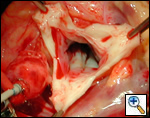

Indications for surgery include symptoms of diminished exercise tolerance, syncope, or angina. Other indications would include 1) systolic ascending aorta gradient greater than 50 mm Hg, 2) aortic valve insufficiency, or 3) evidence of compromised coronary artery perfusion. These patients should undergo surgery at a relatively early age because of the detrimental effect of the high proximal aortic pressure on the coronary arteries with the possibility for accelerated atherosclerotic changes. These patients typically have a thickening of the aortic wall at the sinotubular junction. This abnormal thickening may extend into the ascending aorta and even into the aortic arch. In some patients, this abnormal thickening creates stenosis of the coronary ostium.

The operative approach is through a median sternotomy with the use of cardiopulmonary bypass and bicaval venous cannulation. The first dose of cold blood cardioplegia is antegrade; the remaining doses are retrograde.

High ascending aortic cannulation adjacent to the innominate artery for maximum exposure of the ascending aorta and to allow length for positioning of the patch in the ascending aorta.

First coronary sinus incision in noncoronary sinus to facilitate exposure of the incisions into the coronary orifice sinuses.

In most cases, the right coronary artery sinus should be opened to the left of the coronary orifice and the left coronary artery sinus to the right of the coronary orifice. Occasionally one may not have enough room between a coronary orifice and the aortic valve; in this case the incision site should be tailored to the situation.